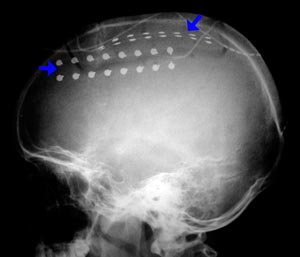

Figura 94 - Radiografia obtida após a cirurgia demonstrando as placas subdurais implantadas.

Figura 98 - Radiografia obitda após a cirurgia demonstrando as placas subdurais implantadas.